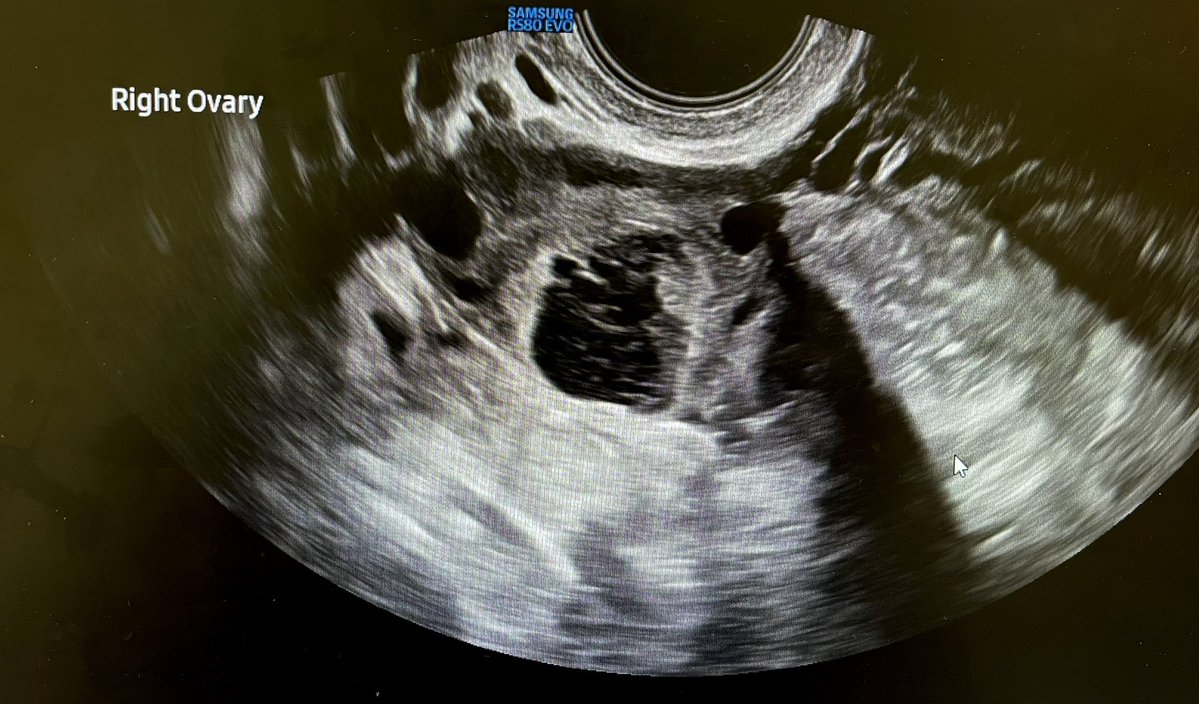

Corpus luteum cysts are physiological. Normal variants. Repeat scans are not required. @Rad_Munagi